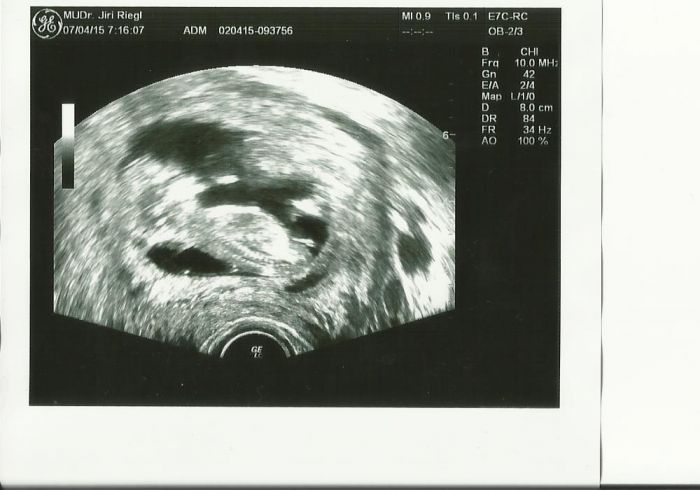

BArbar já jsem to takto měla dvakrát. Vždy týden zpoždění duch na testu a potom ms. Embryjko se prý neudrželo,ale to nemusí být tvůj případ. Po druhé jsem měla ty dvě čárky skoro stejné a stejně přišla ms. Tak jsem si řekla,že budu počítat s každou ms a vše jsem úplně vypustila z hlavy. V lednu jsem měla ms naposledy. :-) V únoru už nedorazila a to jsme se s manželem tulily jen jednou, protože potom nebylo kdy a to bylo tak 5 dní před ovulkou :-) Dneska jsem 12+1 a příští úterý jedu do Brna na první velký utz. Včera jsem byla u svého doktora a vše v pořádku. Přikládám fotku. Pravidelně vás pročítám jen jsem chtěla mít jistotu než vám napíši jak se máme. Krásný den přeju všem